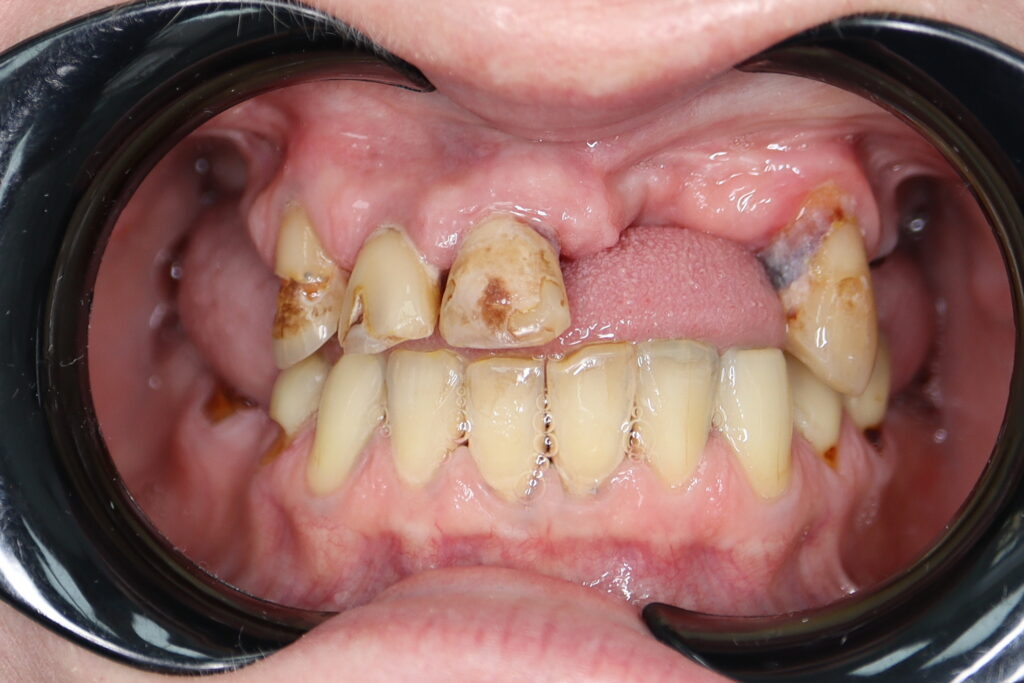

Результаты

Стоимость всего комплекса: 3500 USD (цена указана ориентировочно по курсу НБРБ на день оплаты)

результат тотальной имплантации